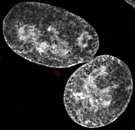

Die Abbildung (Fluoreszenzmikroskop) zeigt das Innere einer Krebszelle nach fehlerhafter Zytokinese: Man sieht zwei Zellkerne (weiss) und vier rote Punkte, die zwei Zentrosomen markieren, die jeweils aus zwei Zentriolen aufgebaut sind. Zentrosomen sind wichtige Organelle, die das Zytoskelett in der Zelle organisieren und die nach einem Zytokinesefehler doppelt vorkommen.